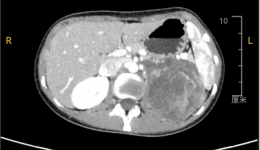

• 术业求精 | 23岁姑娘“怀”10cm巨瘤,我院微创手术“拆弹”成功,美丽不留痕

术业求精 | 23岁姑娘“怀”10cm巨瘤,我院微创手术“拆弹”成功,美丽不留痕

一位23岁的年轻女性,体重仅43公斤,平时进食量不大,一直以为只是自己“胃口小”,直至在一次单位体检中,发现左侧肾上腺区域存在一个10×8×7厘米的巨大肿物,胃和脾脏均已受到明显挤压。医学上,肾上腺肿物若直径超过6厘米,恶性的可...